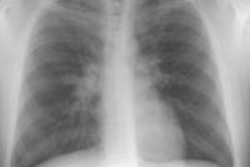

Intrathoracic lymphoproliferative disorders (LPDs) span a spectrum of benign lesions to those that are frankly malignant or have a malignant potential. The clonality of lymphoid populations is helpful in separating benign from malignant disorders. Polyclonality is usually reflective of benign disease, while monoclonality is usually indicative of malignancy. Stimulation of bronchus-associated lymphoid tissue (or BALT) and the Ebstein-Barr virus (EBV) are thought to play key roles in these disease processes. It has been postulated that the EBV genome may act as a stimulant, either as a primary or reactivated agent, particularly in disorders such as infectious mononucleosis and the post-transplant lymphoproliferative disorder.

Several generalizations have been made regarding the LPDs. These are: 1- older symptomatic patients have a more aggressive disease (i.e., lymphoma); 2- benign LPDs tend to be focal (i.e., lung or lymph nodes) and pleural effusions are rare in benign disease; and 3- the post-transplant LPDs may have a variety of radiographic findings (i.e., infiltrates, masses, and/or adenopathy). The site of disease may also provide a clue to the diagnosis. Parenchymal lung abnormalities are found in association with plasma cell granuloma (pulmonary pseudotumor), pseudolyphoma, and lymphatoid granulomatosis (angiocentric immunoproliferative lesion). While mediastinal disease suggests Castleman's disease, infectious mononucleosis, or angioimmunoblastic lymphadenopathy.